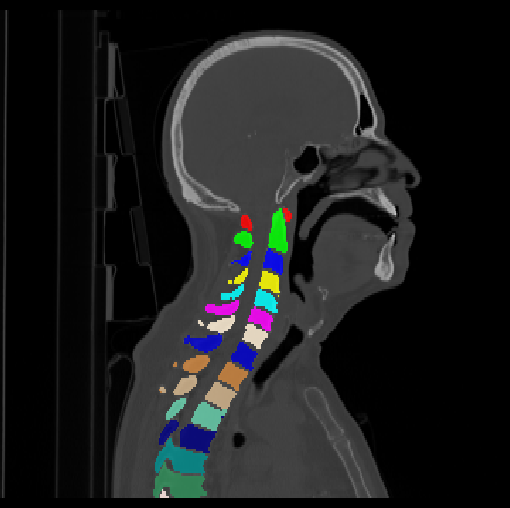

HNSCC-3DCT-RT. This sub-dataset contains three-dimensional (3D) high-resolution fan-beam CT scans collected during pre-, mid-, and post-treatment using a Siemens 16-slice CT scanner with a standard clinical protocol for 31 head-and-neck squamous cell carcinoma (HNSCC) patients (Bejarano et al., 2008). These images are in a DICOM format.

Images

GT

Predictions

3.2.2 Qualitative results.

Some visualization results are presented in Fig. 4, where we can observe that the baseline model can achieve excellent segmentation results. Nevertheless, some failed predictions occur when spinal diseases exist, especially sacral lumbarization and lumbar sacralization. Besides, the image’s resolution of Z direction is closely related to the results, and a lower resolution leads to worse results. Maintaining a reasonable performance for a low resolution is a research challenge. Image superresolution (Peng et al., 2020) might be worth exploring.